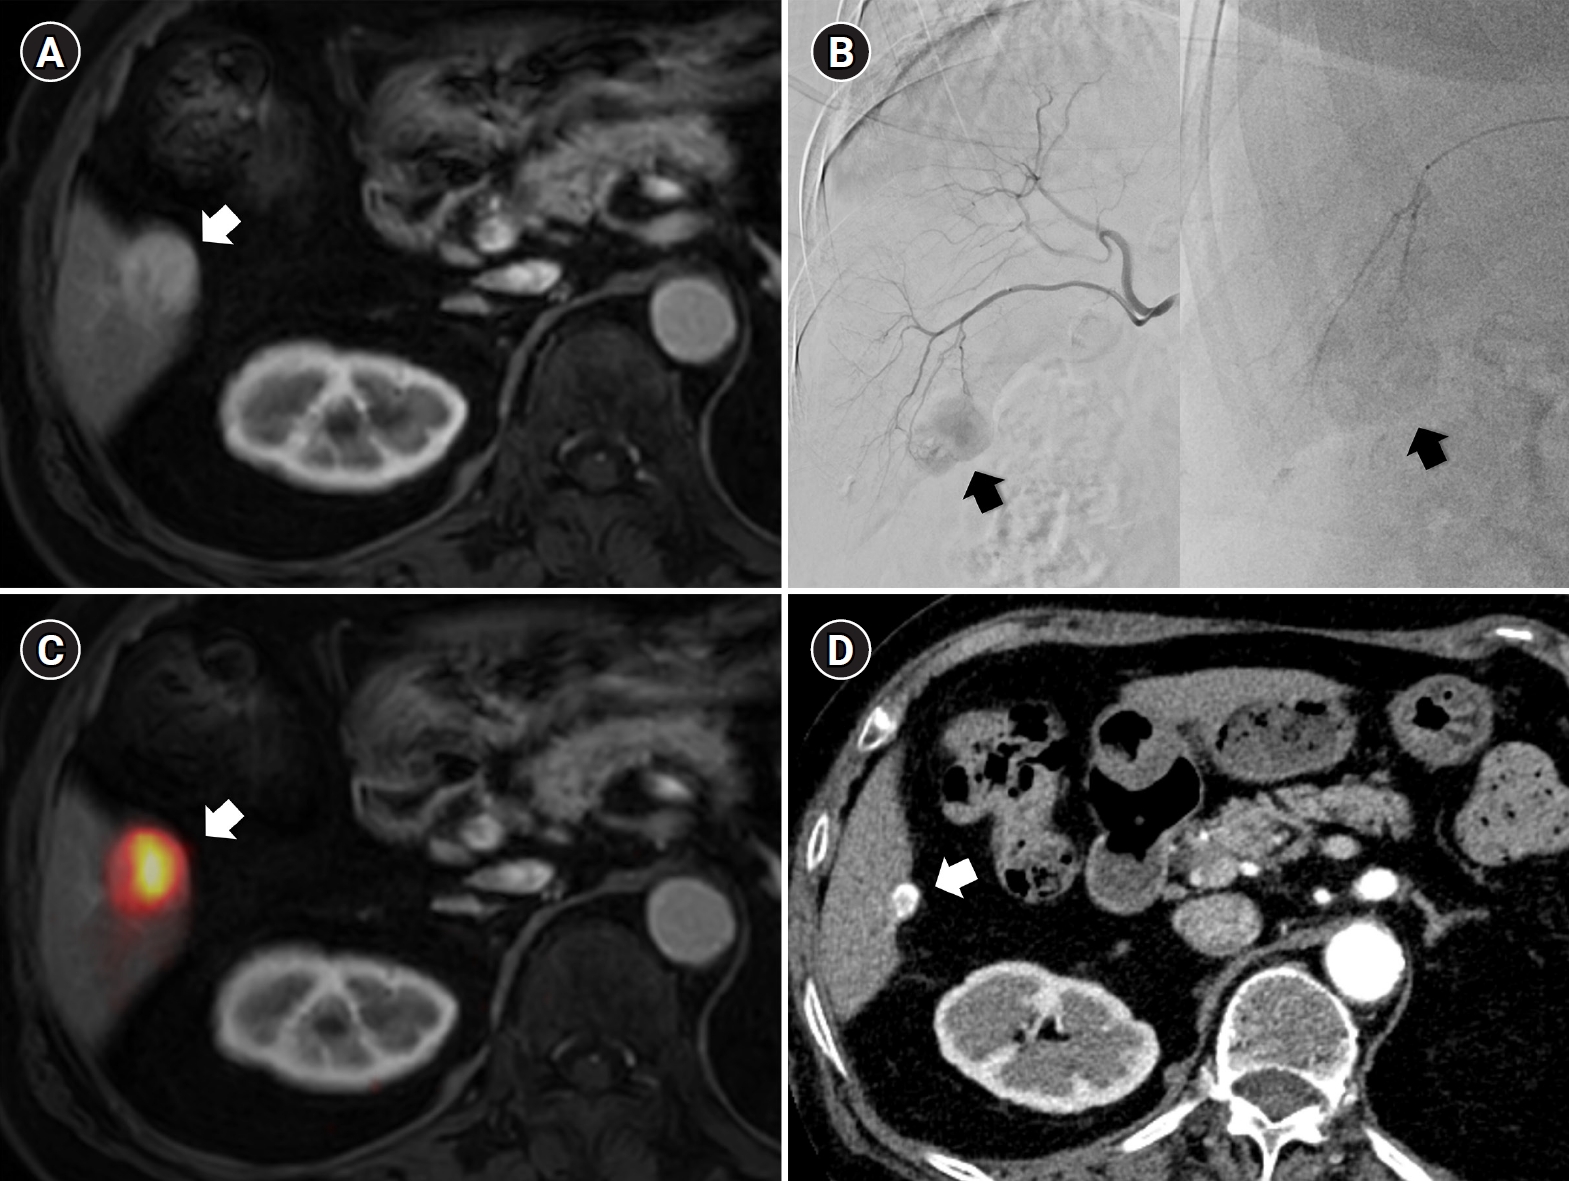

Radiation major hepatectomy in a 60-year-old woman with hepatocellular carcinoma. (A) Contrast-enhanced computed tomography (CT) shows a 9.0-cm hypervascular tumor (arrows) with two satellite nodules (not shown) in segments 7 and 8. (B) Cone-beam CT hepatic arteriography shows tumor staining (arrows) supplied by A7 and A8 (arrowheads). A total of 9.11 GBq of glass microspheres was infused via A7 and A8. (C) Post-treatment Y-90 positron emission tomography shows intense uptake throughout the tumor, consistent with complete microsphere coverage, with a perfused liver dose of 355.3 Gy and a tumor dose of 609.9 Gy. (D) Fifty-month follow-up CT shows complete response with dystrophic calcification (arrows), atrophy of segments 7 and 8, and compensatory hypertrophy of the left hepatic lobe (double arrowheads).

Recent advances in dosimetry optimization have markedly improved the therapeutic outcomes of TARE. Radiation segmentectomy and radiation lobectomy have expanded the role of TARE from a palliative treatment to a potentially curative modality. In early or localized HCC, radiation segmentectomy can achieve complete necrosis by delivering ablative radiation doses confined to one or two hepatic segments (Fig. 1). In the LEGACY study, which included patients with solitary HCCs (median diameter, 2.7 cm; range, 1.0 to 8.1 cm), radiation segmentectomy achieved a 2-year complete response (CR) rate of 84% [12]. In the RASER trial, a single-center prospective study conducted in patients with solitary HCCs ≤ 3 cm, the initial objective response rate was 100 % [18]. This outcome was superior to that reported in a Korean retrospective study (2-year CR rates in 1–10 cm HCCs: 66.2% with conventional TACE and 30.5% with drug-eluting bead TACE [DEB-TACE]) and a Japanese randomized controlled trial (3-month CR rates in 1–5 cm HCCs: 75.2% with conventional TACE and 27.6% with DEB-TACE) [19,20]. Several studies have further demonstrated that radiation segmentectomy can achieve local tumor control rates comparable to those of surgical resection or local ablation, when appropriate dosimetry is achieved [21]. Even for multifocal or bulky tumors, Korean investigators have expanded this principle beyond segmentectomy into a broader concept of radiation “major hepatectomy,” applying ablative doses to larger anatomical territories when disease remains confined and hepatic reserve is adequate (Fig. 2). A Korean study reported a median time to progression of 17.1 months in patients with tumors averaging 11.4 cm in size treated at mean absorbed doses of 418.8 Gy [22]. Radiation lobectomy can also be used when resection is technically feasible but unsafe because the future liver remnant (FLR) is insufficient [23]. By intentionally delivering sufficient radiation dose to non-tumorous parenchyma in the target lobe, contralateral hypertrophy can be induced while simultaneously suppressing tumor progression in the treated lobe [24]. Taken together, these results indicate that territory-based TARE with high radiation dose can serve as a reasonable alternative in patients who are technically resectable but medically inoperable, or in those initially considered for resection who later become unsuitable because of comorbidities or limited hepatic reserve [25].